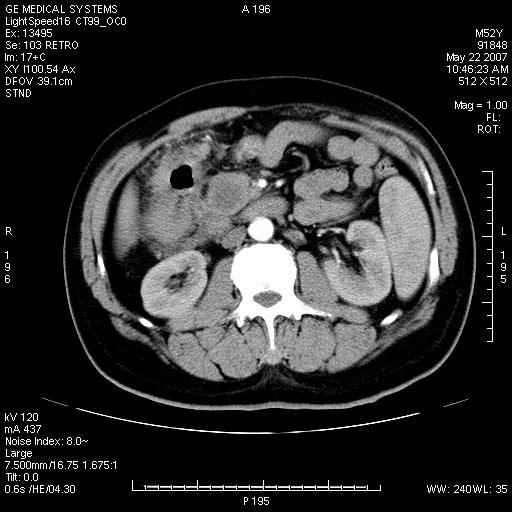

以下是引用余辉在2007-5-22 20:12:00的发言:[br]升结肠管壁明显增厚,增强有静脉期持续增强,结合患者病史,考虑结肠癌可能性大,临近脂肪影密度增高,混浊,恐有肠系膜浸润转移,建议镜检

以下是引用dyqct在2007-5-22 20:43:00的发言:[br]支持结肠肝曲占位性病变(浸润型结肠癌可能性大)。胆总管下端扩张,原因待查。

以下是引用gaoxiao在2007-5-22 20:49:00的发言:[br]考虑升结肠癌向周围侵犯,胰头钩突受侵。